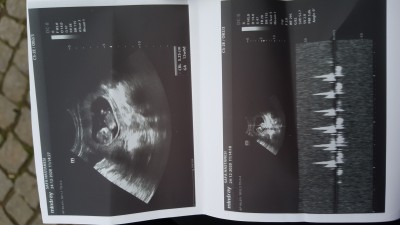

Cinsiyet nedir sizce

cinsiyeti nedir

Gebelik haftası

12

Benim de 16 +3 erkeğe dediler benim ultrason resmiyle çok benziyor erkek olabilir :))